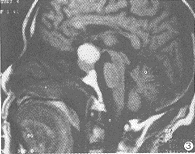

MRI信号特征:9例HPA瘤体在T1WI和T2WI均呈高信号。在T1WI上,6例呈均匀一致的高信号(图1),其余3例呈不均匀的高信号。1例表现散在点状高信号,1例瘤体中心高信号(图2),1例瘤体上半部分高信号,下半部分等信号(图3),。1例EHF引起的垂体出血在T1WI和T2WI呈不均匀的高信号,Gd-DTPA后见血肿轮廓明显强化,肿胀垂体实质略有不均匀强化(图4)。1个月后复查,肿大垂体已明显缩小,大小0.6cm,信号均匀(图5)。

图3 HPA。T1WI矢状位,瘤体上半部呈高信号,瘤体下半部等信号